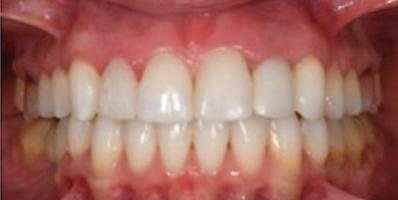

7Dental Tribune Bulgarian Edition / октомври 2022 г. Преди лечението Фиг. 1 Фиг. 4 Фиг. 7 Фиг. 10 Фиг. 13 Фиг. 16 Фиг. 17 Фиг. 18 Фиг. 19 Фиг. 20 Фиг. 11 Фиг. 14 Фиг. 12 Фиг. 15 Фиг. 8 Фиг. 9 Фиг. 5 Фиг. 6 Фиг. 2 Фиг. 3

9Dental Tribune Bulgarian Edition / октомври 2022 г. След лечението За авторите: Д-р Манол Ивчев е създател на COLDY DENT Functional Atelier, завършва дентална медицина във ФДМ, София. Шест години е стажант в ортодонтска практика. Интересите му са изцяло насочени към функционалната дентална медицина. Посещава курсовете на Доусън и Льо Гал. Преминава редица обучения, акредитирани от Института на Славичек във Виена – VieSID. Впоследствие става най-младият инструктор във VieSID. Придобива права да преподава философията на проф. Рудолф Славичек в България. В практиката си се придържа към протоколите на Славичек за функционално лече ние и диагностика, тъй като те са насочени към комплексно лечение. Завършва всички нива за морфология на зъбите и моделаж при Janos Mako. Повишава знанията си по функционална ортодонтия чрез индивидуален курс в Румъния. Д-р Ивчев е и сертифициран зъболекар по лингвална ортодонтия от Катедрата по ортодонтия от Университета по стоматология в Тегу, Южна Корея. Сертифициран е и за лечение на ортодонтски аномалии чрез миофункционални апарати, а също и за ортодонтия, подпомагана от миниимпланти, отново от Университета по стоматология в Южна Корея. Завършва индивидуално обучение по функционална ортодонтия в Университета по дентална медицина в Богота, Колумбия, както и индивидуално обучение по функционална ортодонтия и физиотерапия по про токола на Mariano Rocabado. Има завършено индивидуално обучение по функционална зъботехника и функционален Wax-Up клас I,II и III. Завършва курс за Digital Smile Design и Skin Concept в Люксембург при Christian Coachman, Florin Cofar, Paulo Kano, Josef Kunkela, Livio Yoshinagа. Зт. Leandro Gambogi, Бразилия, завършва зъботехника през 1999 г. Експерт и пионер в дигиталната диагностика. Лектор и инструктор на курсове в областта на дигиталното протезиране. Понастоящем е главен изпълнителен директор и зъботехник в DENTALE DIGITAL LAB. В периода януари 2005 г. – декември 2006 г. завършва бизнес управление и администрация в Methodist University Center Izabela Hendrix. Съавтор на книгата Odontologia Digital: Desafiando os Limites, глава 5: „Дигитално включване във времето. Технология CAD/CAM“. Преминал множество обучения при световноизвестни кли ницисти. Фиг. 51 Фиг. 54 Фиг. 57 Фиг. 58 Фиг. 63 Фиг. 64 Фиг. 65 Фиг. 59 Фиг. 61 Фиг. 62 Фиг. 60 Фиг. 55 Фиг. 56 Фиг. 52 Фиг. 53 Фиг. 66